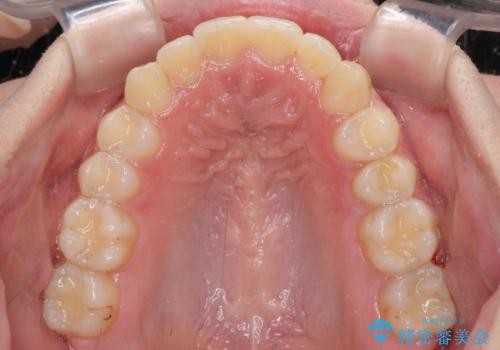

骨格的に左右にずれいている 前歯のデコボコをインビザラインで解消

叢生の程度は中等度であったため、IPR(歯と歯の間を削る)と歯列の側方拡大をメインに、インビザラインを用いて歯列を改善することとしました。

右側の咬合改善を目標に様々な手法を用いましたが、骨格的なズレによる不正咬合はインビザラインでは改善することができませんでした。